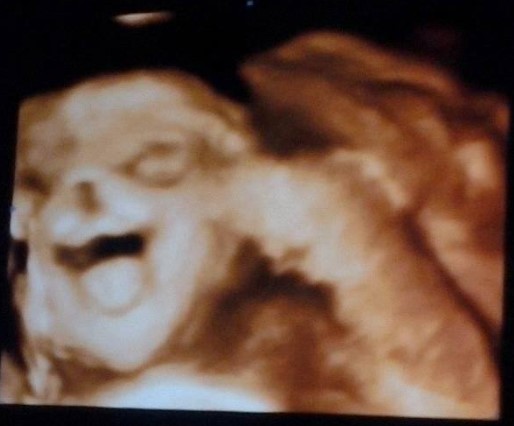

Ecografía de 27 semanas de gestación.

Yaneth G. nos ha enviado la eco de su bebé. Mi reina Sara Isabel de 27 semanas riéndose y con la lengua afuera.